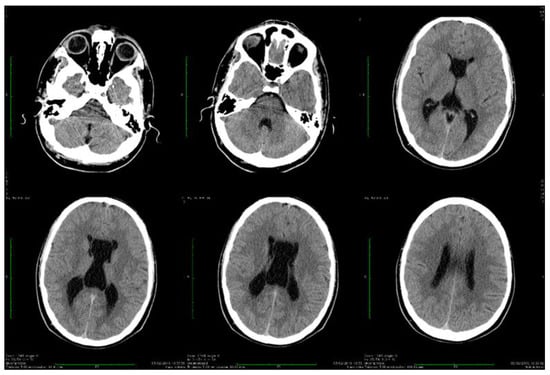

| Stoian et al. (our own case) | Case report | Male/4.5 months | Tonic seizures; later in evolution a left facial hemi spasm | 31 years | Reduced visual acuity (myopia), one and a half syndrome with left abduction nystagmus, left facial hemi spasms, divergent strabismus, flaccid tetra paresis, bilateral inconstant Babinski sign, gait instability, truncal ataxia, | Mild facial dysmorphism with thin upper lip and slightly spaced teeth | Social isolation, bradypsychia, bradylalia, echolalia, minimal linguistic baggage, behavioral stereotypes, MMSE17 points | Cryptorchidism | EEG: Poor unmodulated alpha activity, frontal intermittent theta activity; sharp waves and sharp peaks on the left central, parietal and temporal derivations | Brain CT: generalized sufferance pf white matter; cavum septum pellucidi, enlarged ventricular system, cerebral and cerebellar atrophy. Brain MRI performed before hospital admission: severe cerebral and cerebellar atrophy, vermis hypoplasia, supratentorial and infratentorial demyelinating lesions, cavum septum pellucidi, severe enlargement of the CSF spaces | Valproic acid, later replaced with levetiracetam and after a while with brivaracetam | The seizures disappeared under treatment being seizure-free since childhood; a left facial hemi spasm occurred lately |